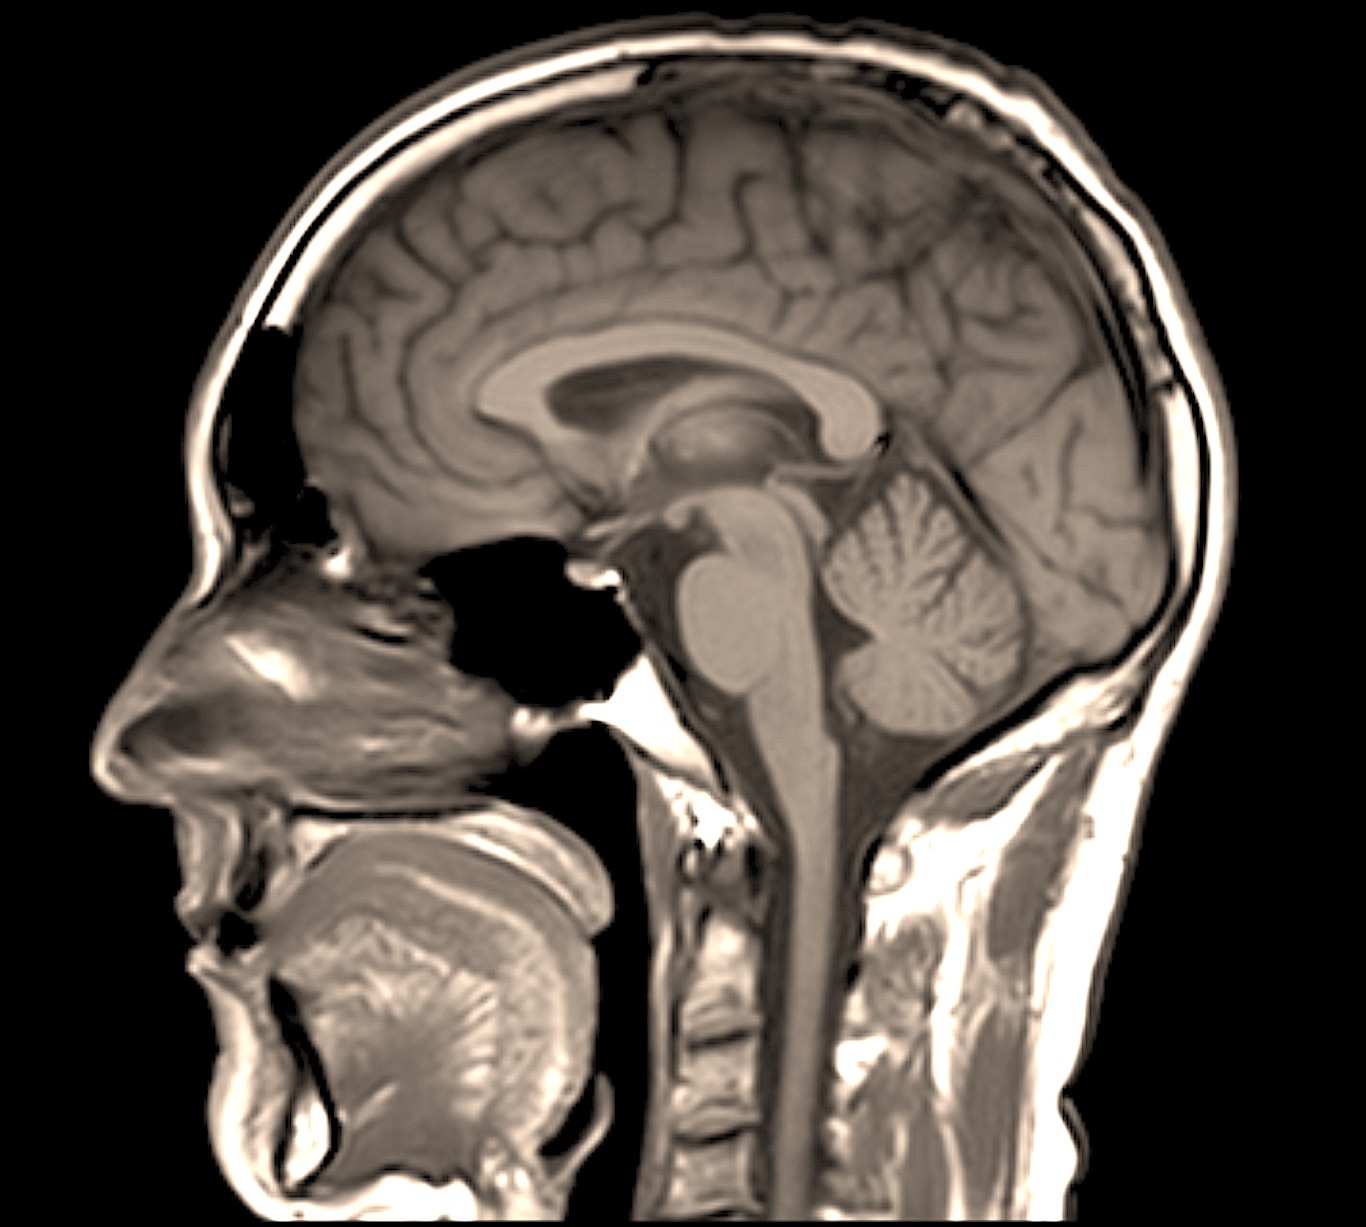

The MRes is designed to equip you to acquire the experience and the skills needed to enter a PhD programme or to move on to careers where advanced research experience will help you. It is an excellent training opportunity for both biological and veterinary graduates and addresses both basic and clinical problems in the biosciences, with applications in veterinary and human medicine. Research areas span cell and molecular science, whole animal physiology and population medicine.